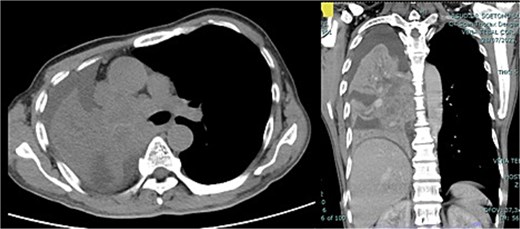

The patient's general condition is good. Laboratory findings indicated normal levels of hemoglobin (12.6 g/dl), platelets (447 000/μl), prothrombin time (14.9 s), and activated partial thromboplastin time (34.9 s). CT scan results showed an enhancing solid mass of the right lung extending to the entire right lung (Fig. 1). The patient was diagnosed with right lung cancer T4N2M1a stage IVA with right lung atelectasis.

CT scan thorax with contrast showed enhancing solid mass measuring ±9.6 × 9.5 × 14.5 cm in the centre of the right lung extending to the entire right lung, middle, and subcarinal mediastinum mass.